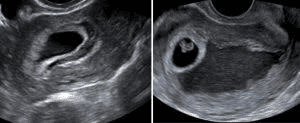

Tụ dịch màng đệm khi mang thai có ảnh hưởng thai nhi không?

Em bị tụ dịch màng đệm từ khi mang thai đến khi thai được 12 tuần vẫn chưa hết (tụ dịch có giảm dần từ 29mm nay xuống còn 8mm), không đau bụng, không ra huyết. Qua siêu âm thai vẫn phát triển bình thường.